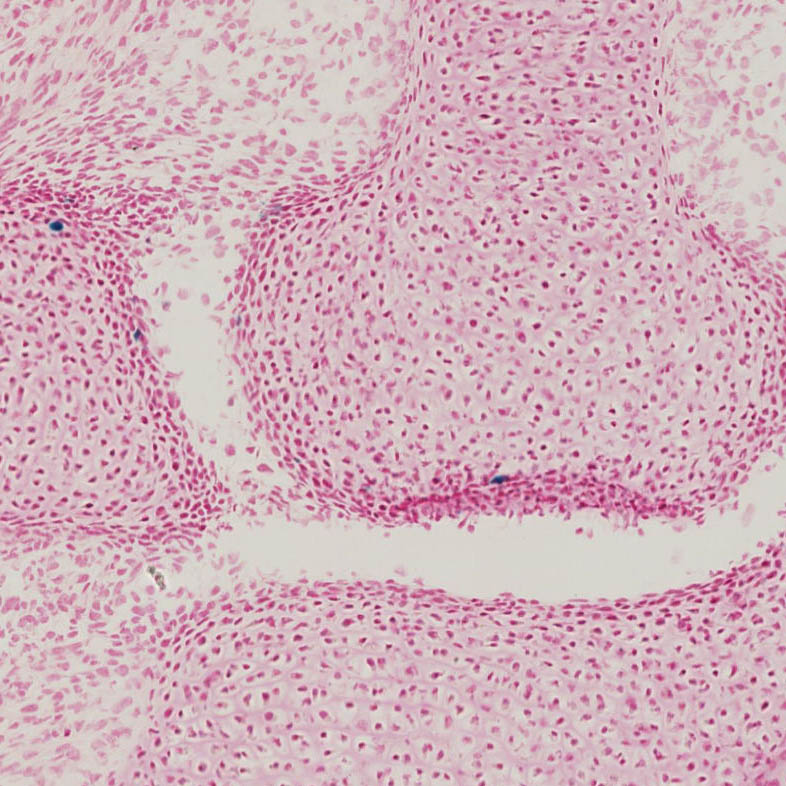

Images

Drag images to compare to others or to data in the table below. Drag corners to resize images for more detail.

Recombinase Activity